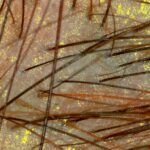

- Tricoscopía/capilografía y exámenes complementarios, si es necesario, para identificar el tipo de alopecia.

Utiliza luz LED de espectro específico para estimular el metabolismo celular, reducir la inflamación y favorecer el crecimiento de cabello más fuerte y saludable. - Tricoscopía. Examen médico no invasivo que permite observar en detalle el cuero cabelludo y los folículos pilosos mediante un dermatoscopio digital.

IMÁGENES EXAMEN CAPILAR